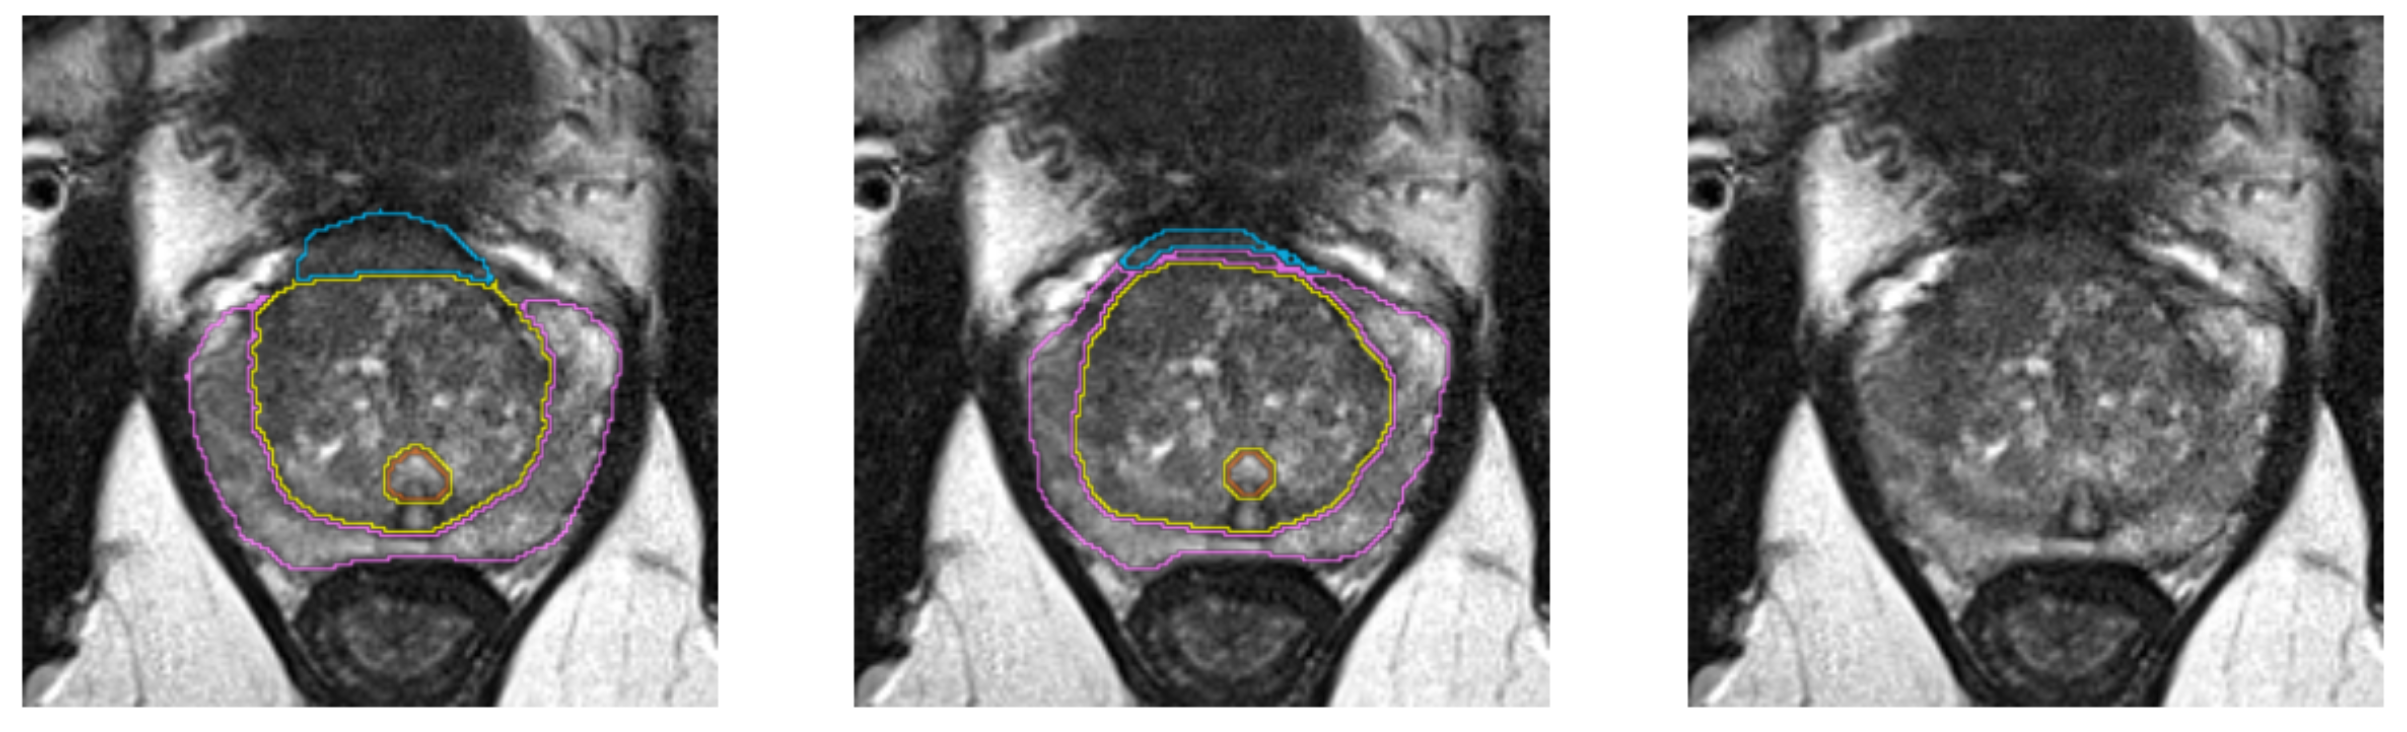

Multi-Label segmentation of anatomic prostate zones in MRI

The goal of this project is to evaluate and extend variants of a volumetric CNN for multi-label segmentation of prostate zones in MR images. The prostate zones are essential for lesion classification and therapy planning. After successful segmentation, a sector map could be extracted that is used for PI-RADS reporting. This has the potential to automate and better standardize prostate lesion location reporting. This project is a continuation of the project that we started in last Winter Project Week. We already have results, but especially in one zone, the algorithm does not work very well and is not stable.

Illustrations